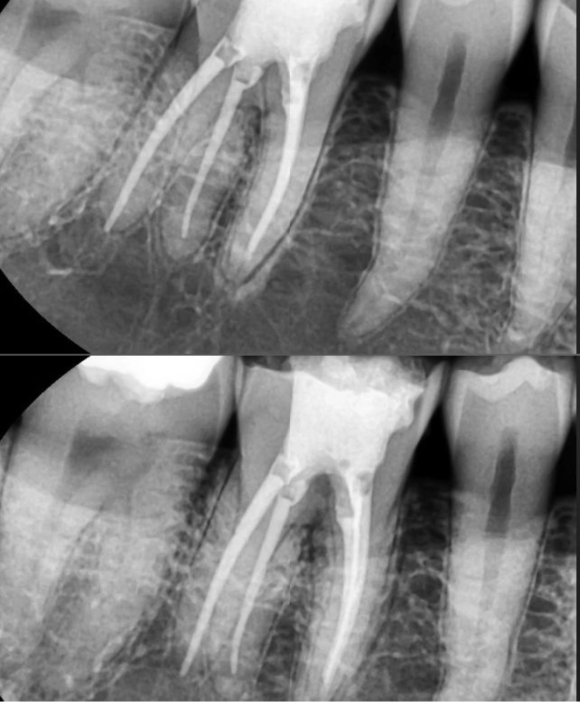

2022.3.9 어금니 신경치료 마무리

리더스진치과는 보존보철 과장님과 함께 협진으로 많은 진료를 원칙적으로 하고 있습니다.